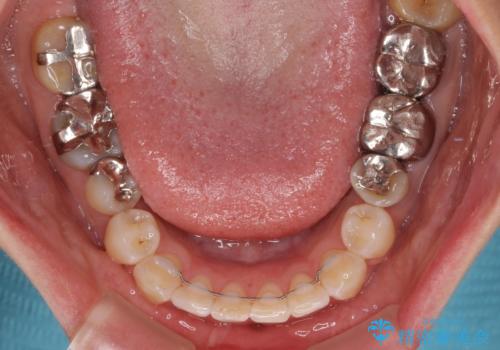

矯正治療は、歯の後戻りを抑制するために、治療終了後も保定装置をしっかりと使用していただくことが必須であるため、気になっている下顎だけを整えることで、その負担を半減できると考え、下顎のみの部分矯正として治療を行うこととしました。

当院では治療前の歯列が整っていない限り、下顎前歯の舌側をワイヤーで固定するようにしています。下顎のみの部分矯正としたことで、マウスピース保定の負担を軽減することができました。

上顎は、失活して歯の色が変色しているため、将来的に補綴治療で自然な口元に仕上げていきたいとのことでした。